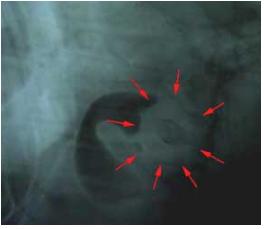

Xrays were taken of the stomach and intestines and they indicated a possible foreign body in the small intestine. Barium was given to the dog, but this failed to move through the small intestines confirming that the dog was totally blocked.

The dog went to surgery to remove the unusual item in the intestines.